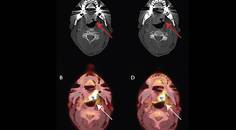

Critical Bilateral Carotid Artery Disease Presenting as Hemichorea